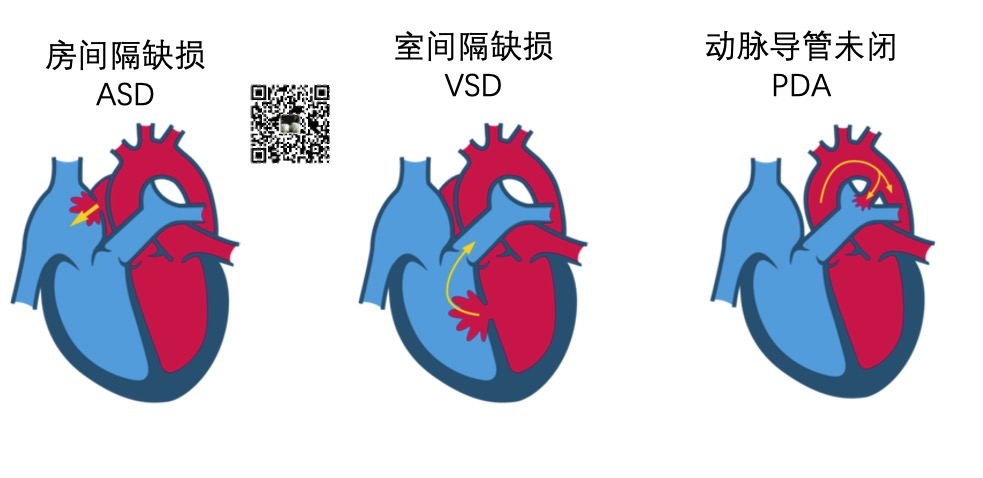

先天性心脏病

先天性心脏病主要包括室间隔缺损、房间隔缺损、动脉导管未闭,法洛氏四联症等。

房间隔缺损 (Atrial Septal Defect ,ASD)是指分隔右心房和左心房的壁上的出现破损。ASD会增加流经肺部的血液量,随着时间的推移,会损坏肺部血管。

室间隔缺损 (Ventricle Septal Defect ,VSD)是指分隔右心室和左心室出现破损。VSD使得血液可以从左心室渗入右心室,造成更多的血液被泵入肺部,迫使心脏和肺部更加努力地工作。

临床研究表明,VSD是以下疾病的高危风险因子: (1)心力衰竭 (2)中风 (3)肺动脉高压(肺部高血压) (4)心律失常(心律不齐)

动脉导管未闭(PDA)是指心脏的两条主要动脉,即主动脉和肺动脉,之间有一个连接口。通常,这个开口会在出生后不久关闭。如果没有闭合,即发生PDA。

PDA患者的主动脉中富含氧气的血液会肺动脉中缺氧的血液混合。

法洛四联症(Tetralogy of Fallot,TOF)是一种常见的先天性心脏畸形。其基本病理为室间隔缺损、肺动脉狭窄、主动脉骑跨和右心室肥厚。